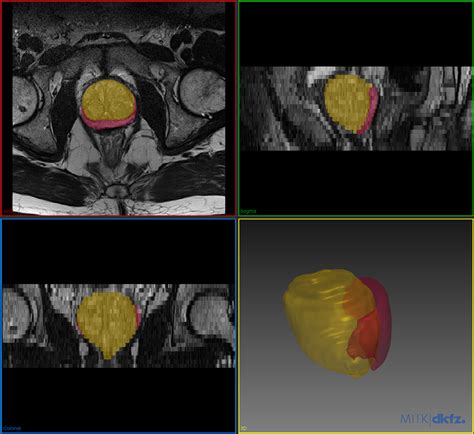

OSCI Imaging offers various services such as: Image Acquisition, Image Processing, and Image Analysis. Image acquisition is the process of getting a visual representation of the subject. Image processing involves modifying images to improve the analysis. This can include removing noise, enhancing contrasts, or other adjustments. Image analysis is the process of extracting the required information from the images. OSCI Imaging deals with the challenges of handling, analyzing, and interpreting scientific image data. The field of OSCI Imaging is broad, and it includes many techniques. For example, Image segmentation, which is used to divide an image into meaningful parts, and feature extraction, which involves identifying the image features of interest, can improve image quality. It uses tools and methods to convert raw images into useful data that can be interpreted and analyzed. OSCI Imaging, by focusing on imaging-related issues and giving tools, improves the quality and the usage of scientific images.

OSCI Imaging is a core element in a variety of scientific fields, and it is a key instrument in research. OSCI Imaging supports research areas, including: Medical imaging (CT scans, MRIs, etc.), Microscopy (light, electron, etc.), Remote sensing (satellite imagery). It has its own advantages, like Visual data representation : OSCI Imaging offers an easy way to understand the image data. Data analysis : Using OSCI Imaging, it is easy to extract all of the needed information from the images. Efficiency : OSCI Imaging can save time and effort by automating processing. OSCI Imaging plays a key role in making sure that images are accurate, meaningful, and useful for scientific research and discovery. It allows researchers to get more out of visual data and advance our understanding of the world around us. In the end, OSCI Imaging is the key to getting good images that give us valuable insights and lead to breakthroughs.

One of the main areas where they connect is in image data annotation and analysis . Researchers can upload image data from various sources (like microscopy or medical imaging) and link them to relevant biological data found in NCBI databases. This is where the magic happens! For example, when analyzing microscopy images of cells, you can use OSCI Imaging tools to process and segment the images. You can then use the NCBI databases to find information related to the gene expression or protein localization within those cells. The main point of this procedure is to improve data analysis, and it gives the ability to gather a lot of information. OSCI Imaging gives you the means to analyze images, while NCBI gives you context.

Data integration is another key element where these two come together. The integration enables the linking of image data with other biological information. Linking image data with other biological information helps in forming a clear understanding of biological processes. OSCI Imaging is used to analyze images, and NCBI is used to find details on genetics, proteins, and literature. For example, using OSCI Imaging to examine medical images can be combined with genetic data acquired from NCBI to analyze the connection between image characteristics and gene expression. OSCI Imaging and NCBI work in collaboration to make information more accessible and useful by integrating data from various resources. Integration of data helps in producing valuable insights that can lead to discoveries. The ability to join image data with other details makes the work more effective and useful. Researchers may use the tools of OSCI Imaging and NCBI to build integrated data, which helps in the advancement of scientific research.